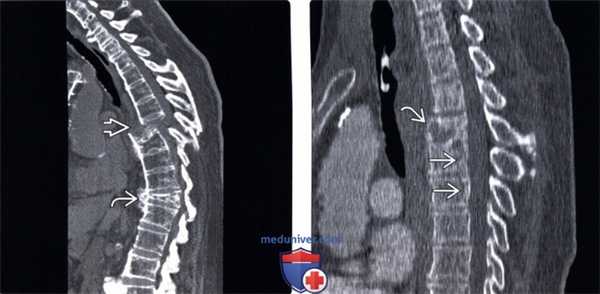

(Слева) КТ, сагиттальный срез, пациент с анкилозирующим спондилитом: гиперэкстензионный переломовывих. Нижележащий отдел позвоночника смещен кпереди, что привело к критическому стенозу спинномозгового канала. Каудальней виден компрессионный перелом позвонка.

(Справа) КТ, сагиттальный срез: косой перелом тела среднегрудного позвонка с незначительным расхождением фрагментов, свидетельствующим о гиперэкстензионном характере повреждения. В области двух нижележащих позвонков видны вертикальные линии переломов.